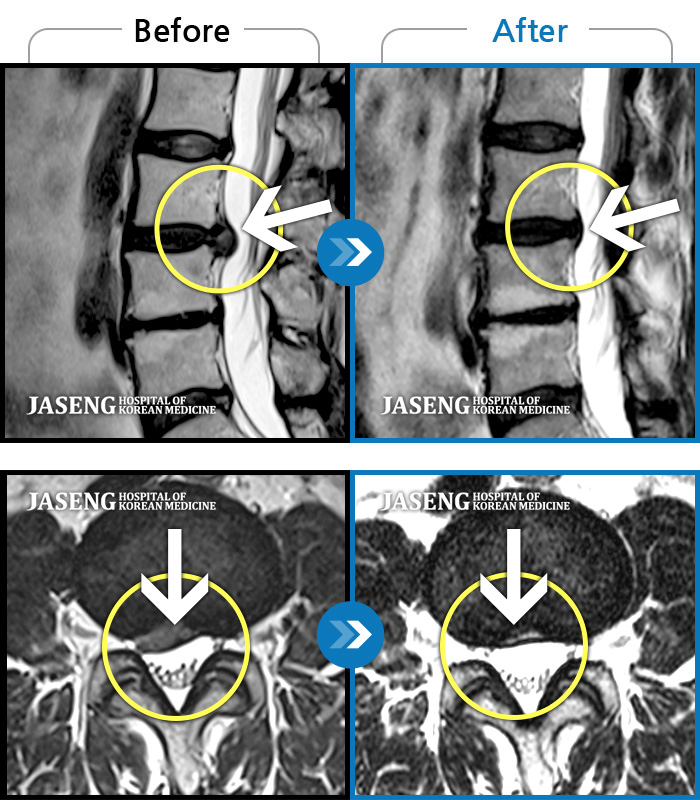

Before

After

허리 통증과 함께 발끝 저림이 1년 이상 되었으며 최근 1-2개월 사이에 증상이 급격히 심해져 우측 다리 앞 뒤가 당기고 힘이 빠져 본원에 내원함

2023.11.20 ~ 2024.08.12